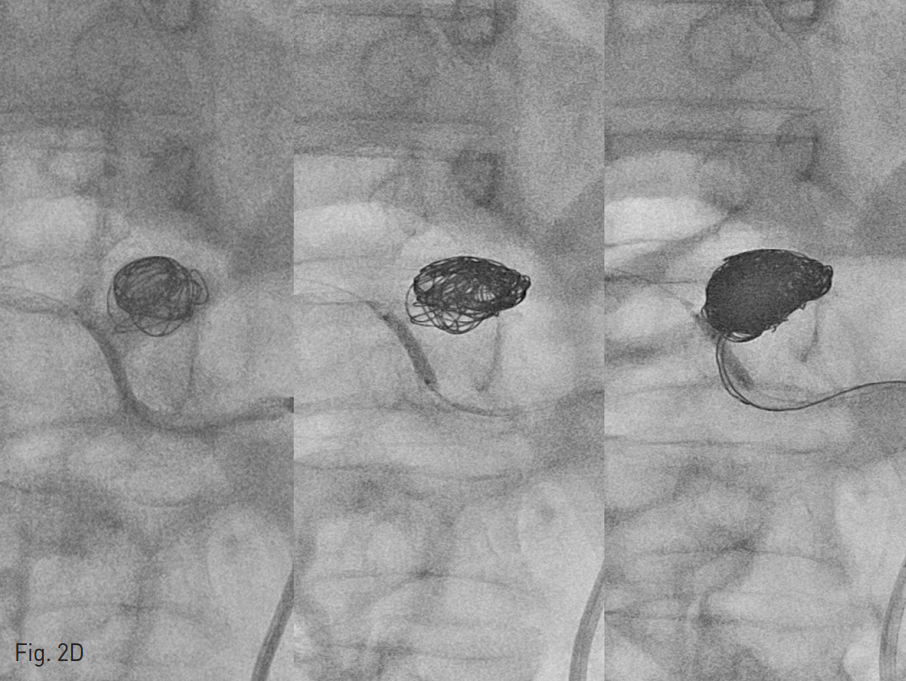

이 되도록 2.5 Fr Renegade (straight type)과 2.5Fr Renegade STS (angled ty pe)를 동시에 insertion하여 두 개의 catheter tip이 각각 동맥류 내부의 다른 위치에 위치하도록 navigation시킴 (Fig 2C). Balloon을 inflation시킨 후, 2개의 microcatheter를 통하여 interlock coils을 사용하여 embolization 시작함. Aneurysm neck으로 coil이 빠져 나오지 않도록 interlock coils을 사용하여 아주 주의 깊게 coil packing을 진행함. 최종적으로 직경 14mm ~3mm 크기의 interlock coils을 모두 24개를 사용하여 동맥류의 내부를 완전히 채움. Follow up celiac angiography에서 동맥류은 coiling packing되어 flow는 전혀 보이지 않았고, proper hepatic artery 의 flow는 유지되어 liver쪽으로 perfusion이 이루어지고 있는 것을 볼 수 있음 (Fig. 2E). Proper hepatic artery가 약간 가늘어 보이나, balloon inflation에 의한 vasospasm의 영향을 고려했을 때, 시간이 지나면 좀 더 좋아질 것으로 생각하고 시술 종료함.

Fig. 2. Balloon-assisted coil embolization

D. The aneurysm was densely packed with total 24 interlock coils